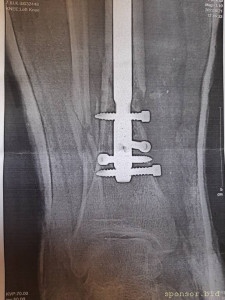

Вот что со мной произошло: летом прошлого 2022 года я неудачно упал, и сломал левую ногу, да так, что всё не закончлось просто гипсом. Перелом был сложным, пришлось делать операцию, ставить биос. Операция прошла с осложнениями, был свищ, нога после операции долго не заживала. Потом сломался крепёжный саморез, стало ещё хуже. Заболела правая нога в колене и бёдре. На приёме у врача сказали нужна операция! И в ближайшее время! Но я на больничном уже целый год, и после такого продолжительного лечения, все мои финансы на нуле. Ходить не могу, спать не могу, мучают постоянные боли. У меня развился сахарный диабет, ноги болят, появилась венозная недостаточность и варикоз. Мне всего 41 год. Получается я останусь инвалидом навсегда... Но у меня есть двое детей 5 и 14 лет... В данный момент я не могу встать на ноги из-за отсутствия финансовых средств. Моя мама Лариса Андреевна, помогает мне по мере своих сил. Ей приходится работать на производстве. Но ей уже 75 лет...

Нужна помощь сыну сотрудницы Не может ходить. - 20230719_135335.jpg

Нужна помощь сыну сотрудницы Не может ходить. - 20230719_135402.jpg